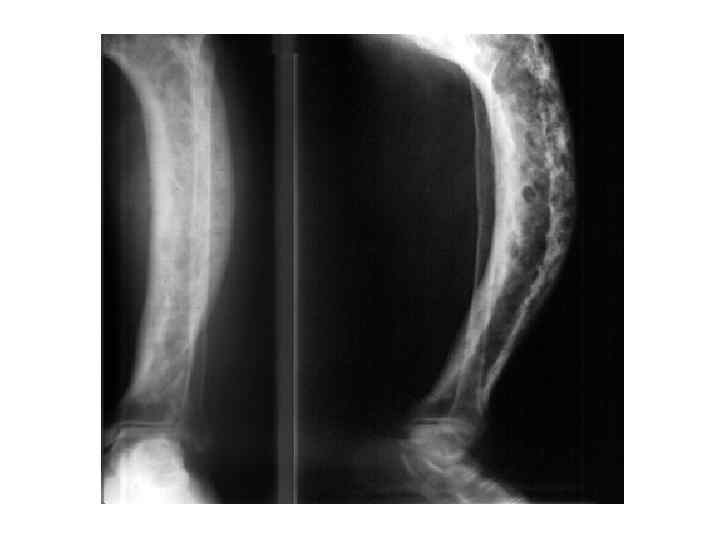

Рентгеновские снимки и визуализация болезни Педжета

Раздел: Мудрость в объективе